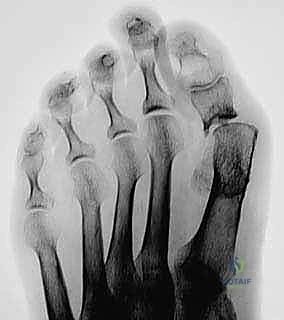

FIG 1 • A failed Keller’s resection arthroplasty.